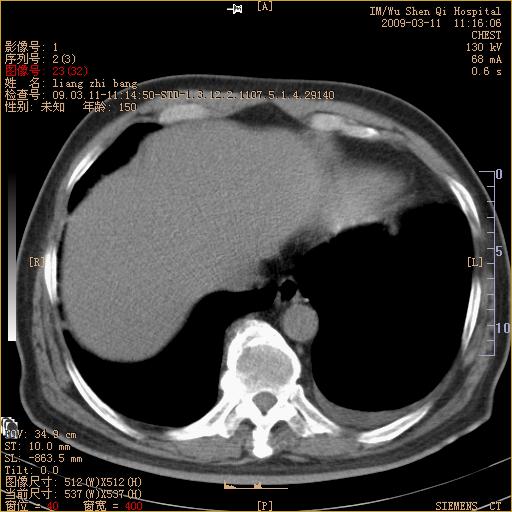

标题: CT18604:男,60岁,咳嗽一月余 [打印本页]

标题: CT18604:男,60岁,咳嗽一月余

1)考虑左肺上叶中央型肺癌并左肺上叶肺不张;建议必要时行纤支镜检查进一步明确诊断。2)左侧胸腔积液。

考虑左肺上叶中央型肺癌并左肺上叶肺不张

肺门肿块、支气管开口闭塞伴肺不张及胸水!典型的中心型肺癌变现!

1、左肺上叶中央型肺癌并上叶阻塞性肺不张。

2、左侧胸腔少量积液,右侧胸膜轻度增厚。

左肺们肿块并左肺上叶不张。考虑左肺中心性肺癌并左肺上叶不张及左侧胸腔积液